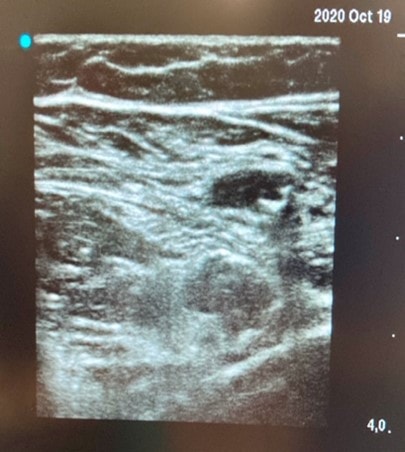

- Colocamos la sonda a nivel de pliegue inguinal. Veremos la estructura pulsátil de la arteria femoral y lateralmente una estructura hiperecogénica de forma ovalada o triangular por debajo de la fascia ilíaca.

- Ligero cabeceo inferior de 10-15 º para mejor visualización.